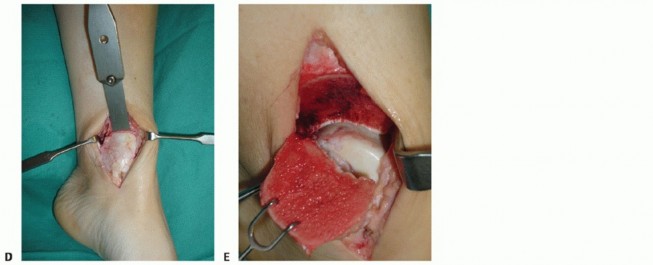

Make a longitudinal incision centered over the medial malleolus ( TECH FIG 1A ). Anterior ankle arthrotomy

Identify the joint line ( TECH FIG 1B ).

Visualize the anterior talus and possibly anterior OLT ( TECH FIG 1C ).

TECH FIG 1 • A. Medial approach is similar to that for open reduction and internal fixation for a medial malleolar fracture. B,C. Anterior ankle arthrotomy. B. Locating joint and performing the medial capsulotomy. C. Medial talar dome visible through the arthrotomy with capsule retracted. This defines the anterior margin for the osteotomy. Rarely, the OLT may be accessed via arthrotomy alone, but this is more common for lateral lesions.

Open the flexor retinaculum (

TECH FIG 1D

).

Identify and protect the posterior tibial tendon (PTT) ( TECH FIG 1E ).